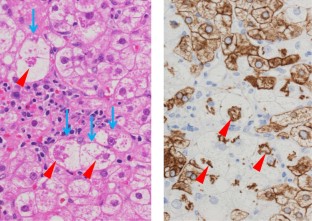

Nonalcoholic fatty liver disease (NAFLD) is based on the concept of pathological morphology as well as clinical findings, and is broadly categorized into nonalcoholic fatty liver (NAFL) and nonalcoholic steatohepatitis (NASH). The differential diagnosis between NAFL and NASH is important because NASH has the potential to progress to cirrhosis and hepatocellular carcinoma. NAFL is simple hepatic steatosis without hepatocellular injury, while NASH is characterized by macrovesicular steatosis, inflammation, and ballooning hepatocytes with a predominantly centrilobular (zone 3) distribution. Liver biopsy is a useful test for diagnosing NAFLD, but it is invasive. Therefore, various noninvasive methods including diagnostic imaging have been developed in recent years. To verify their usefulness, it is necessary to clarify in detail how the pathological findings are reflected in the image findings as imaging and histopathological findings are closely related. We describe the main histological features of NAFLD, i.e., steatosis, inflammation, ballooning hepatocytes, Mallory-Denk bodies, and fibrosis, as well as the evolutional process to liver cirrhosis.

Fig. 2